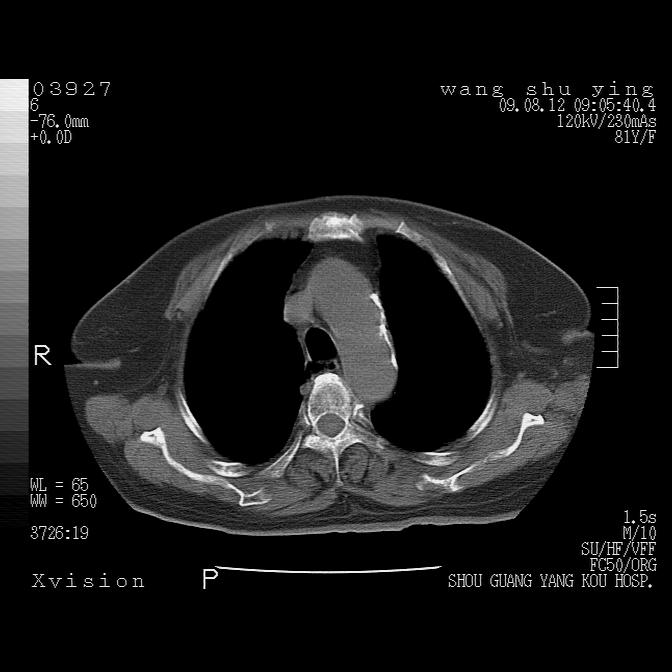

以下是引用帅河马在2009-8-12 12:59:00的发言:[br]两肺感染性病变伴双侧胸膜肥厚。[br]左侧甲状腺腺瘤不除外。[br]腹水+心包积液。[br][br][本贴已被 帅河马 于 2009-8-12 13:14:32 修改过]

以下是引用sdzyy在2009-8-12 18:17:00的发言:[br]两肺感染性病变伴双侧胸膜肥厚。[br]左侧甲状腺腺瘤不除外。[br]腹水+心包积液。[br]支持

以下是引用随光逐影在2009-8-12 19:42:00的发言:[br]1)两肺感染性病变伴双侧胸膜肥厚。2)不排除左侧甲状腺腺瘤。3)肝脏占位性病变;建议行进一步检查。